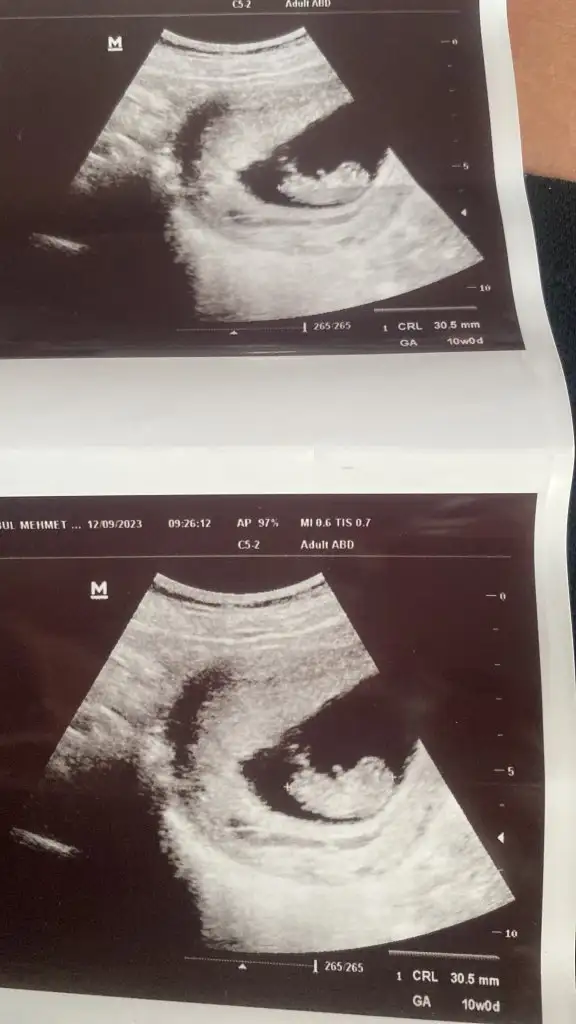

Merhaba burda 10 haftalık hamileyim tahminlerinizi bekliyorum lütfen 🥰🙏🏻

Merhaba bana da yorum yapabilir misiniz? Karından ultrason 10+2 burda 🌸

İyi akşamlar burada 10 hafta 3 gün gözüküyor ultrasona göre sizde saniyeye belli mi ?

Karından ultrason bu arada